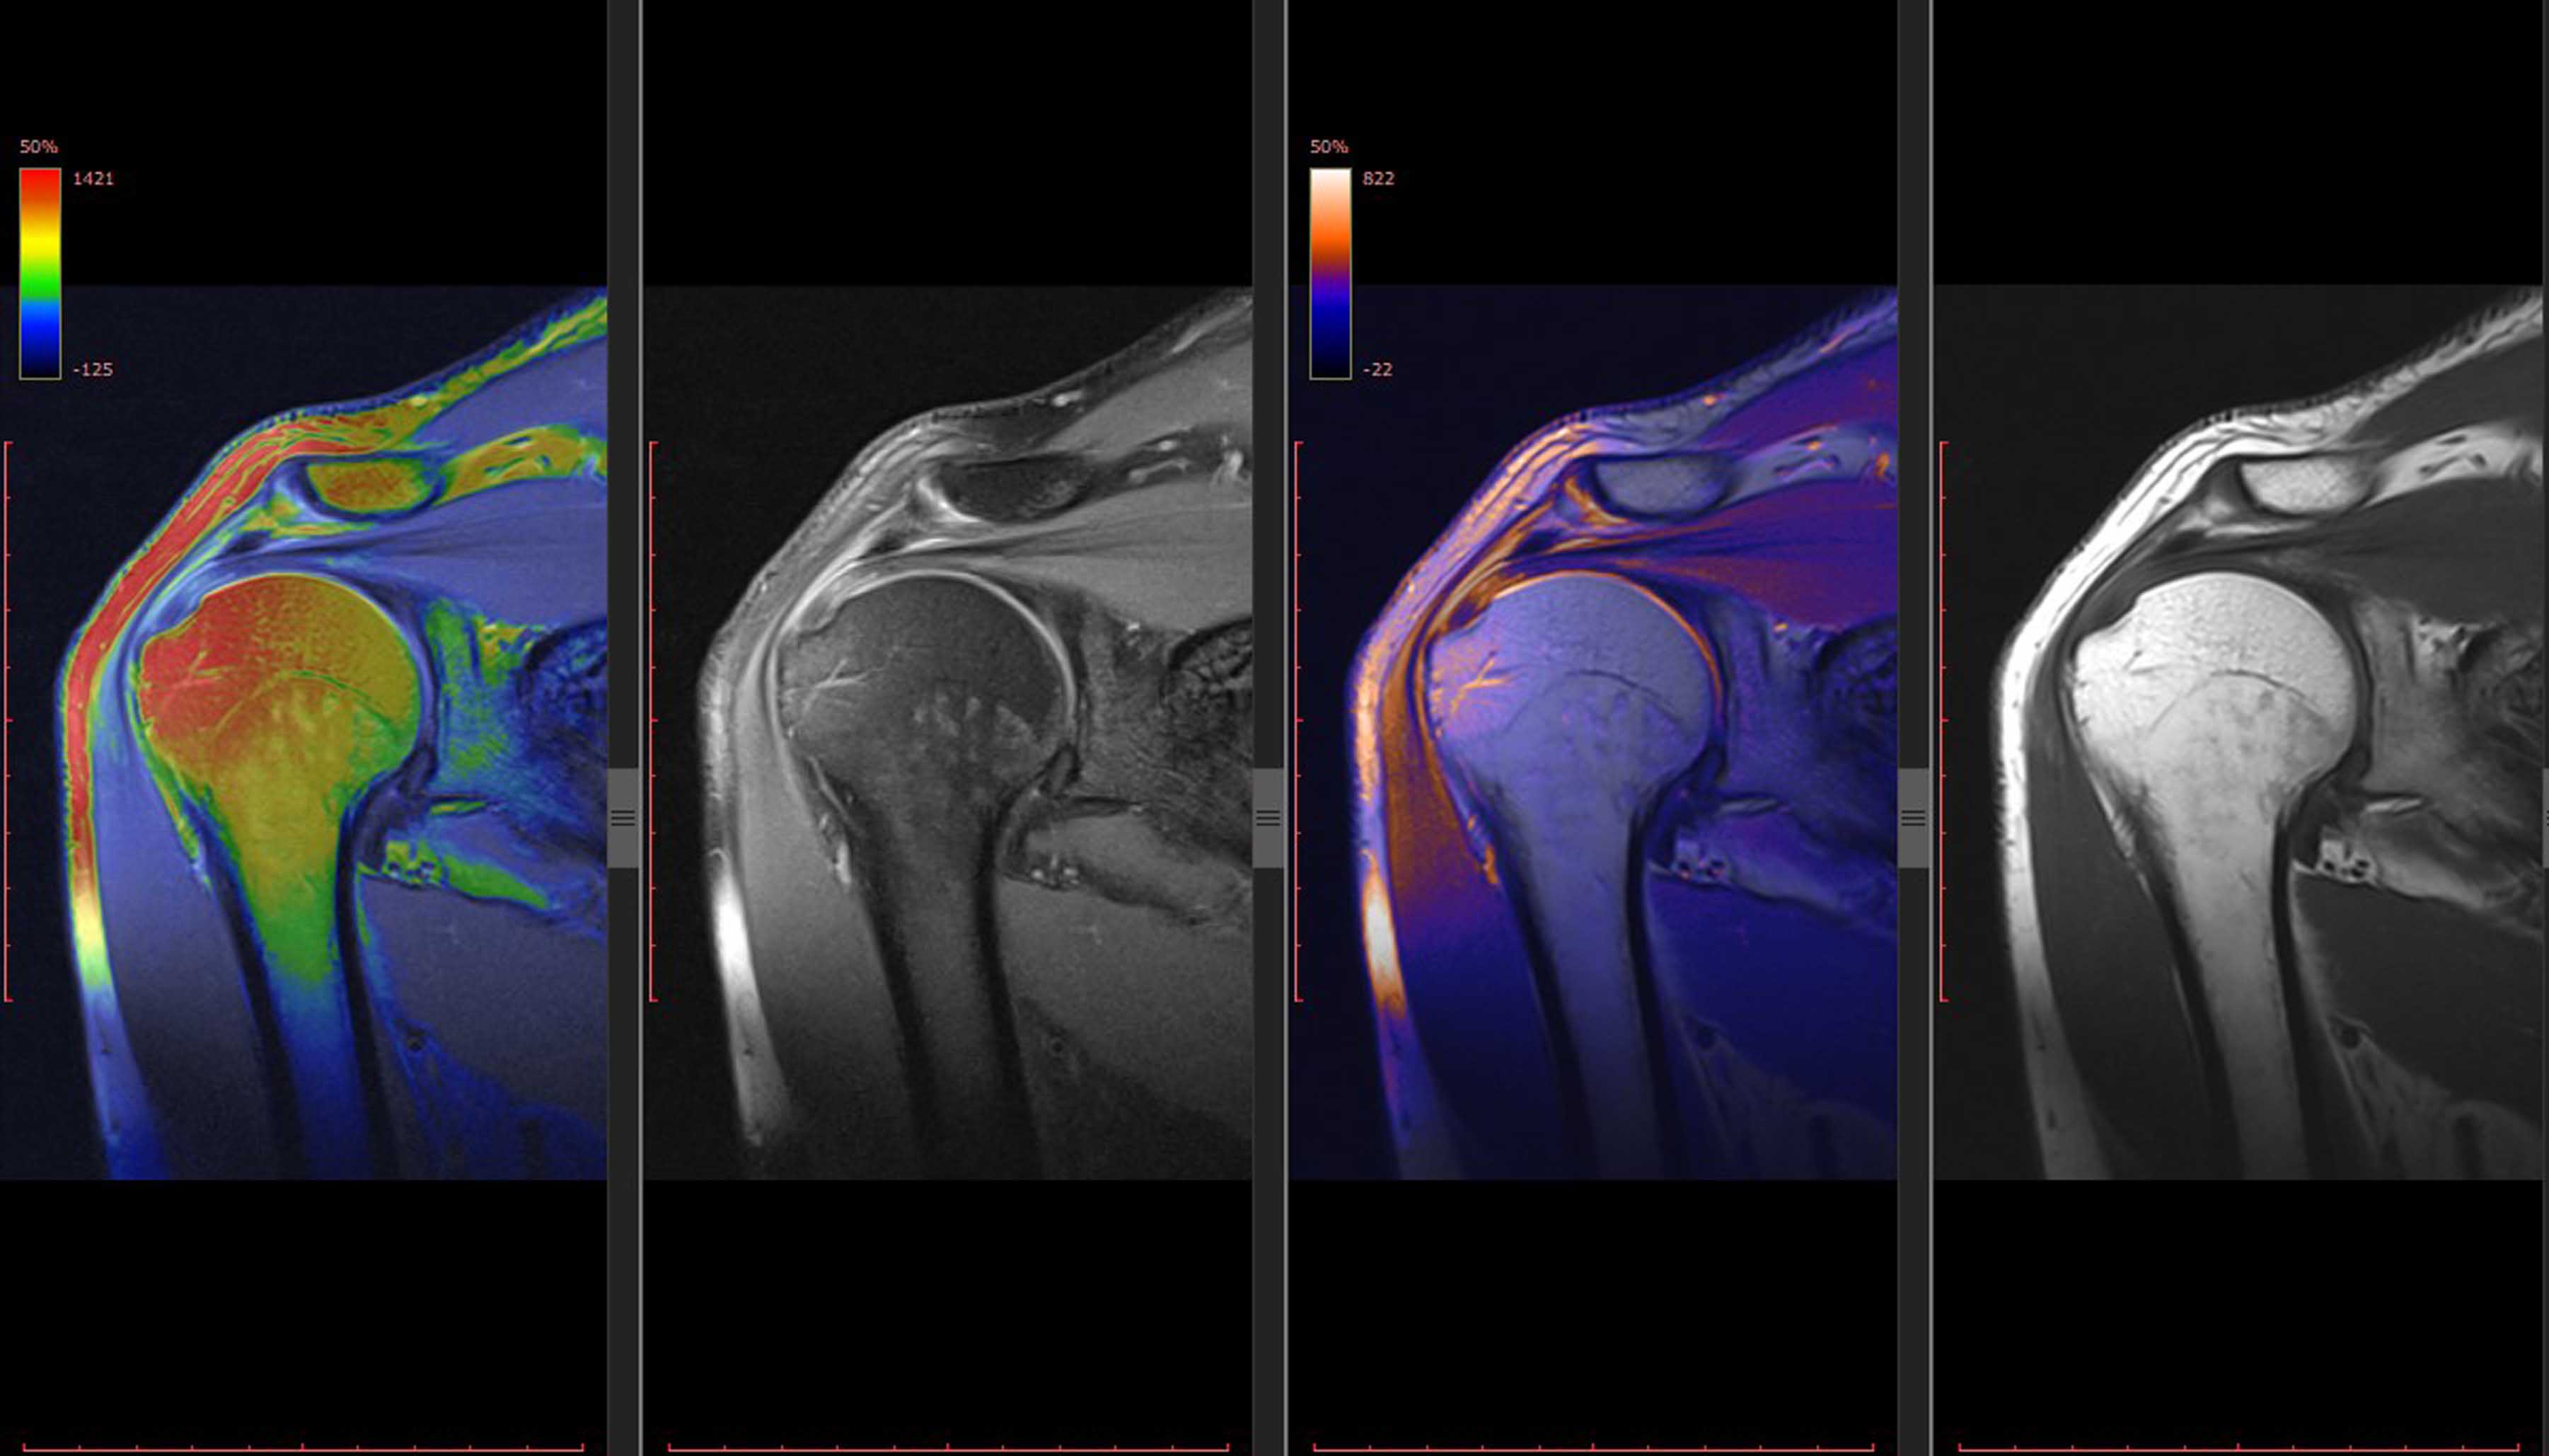

الأمراض الجهاز الحركي كثيرة ومتنوعة، وتمثل طرق وأساليب الأشعة جزءاً محورياً من تشخيصها ومعالجتها، ويمكن أن تساعد الأساليب الموجهة بالأشعة في علاجها. ولذلك يعدّ الفهم التفصيلي لظواهر وإجراءات أشعة أمراض الجهاز الحركي، والروماتيزم والأورام ومشاكل الاستقلاب، جزء بالغ الأهمية للمعالجة المناسبة للمرضى ضمن فريق متعدد التخصصات.

ويهدف برنامج زمالة أشعة تصوير الجهاز الحركي والذي يمتد عاماً واحداً إلى تحقيق هذه المهمة. وبفضل الكمّ الكبير من الإحالات، والأدوات المتطورة، وطاقم العمل الخبير، فإن لدى الطبيب المتدرب فرصاً تدريبية جمّة في هذا المجال الفريد. ويحظى الطبيب بفرصة المشاركة في الأنشطة الجماعية، والمؤتمرات الإكلينيكية، وتدريس الأطباء المقيمين، والمشاركة في الأبحاث.